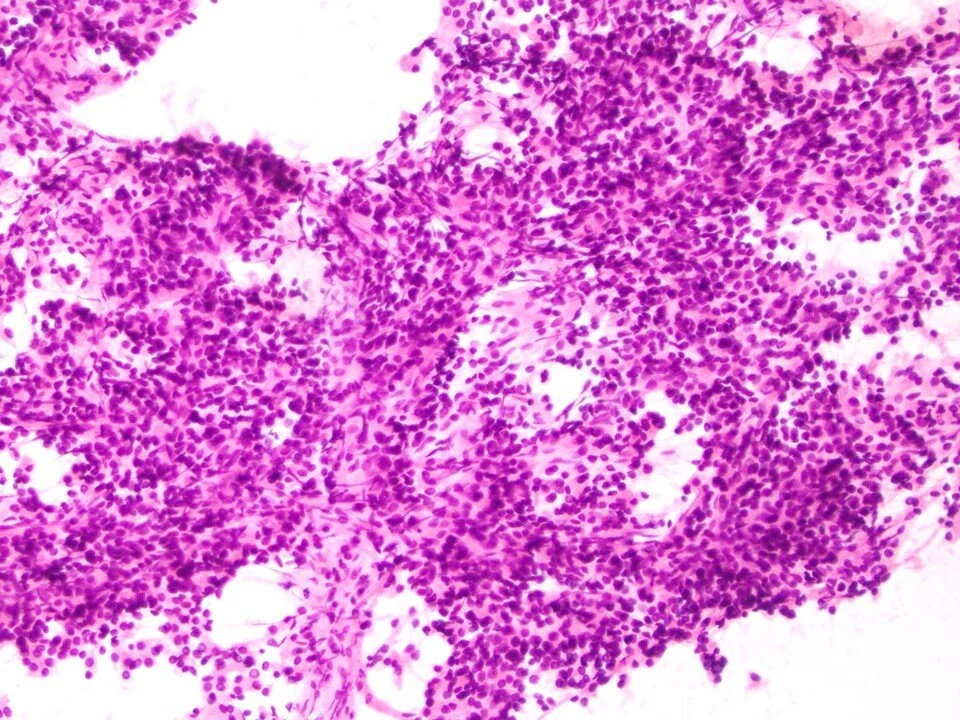

Sclerosing pneumocytoma

Sclerosing pneumocytoma - cell block